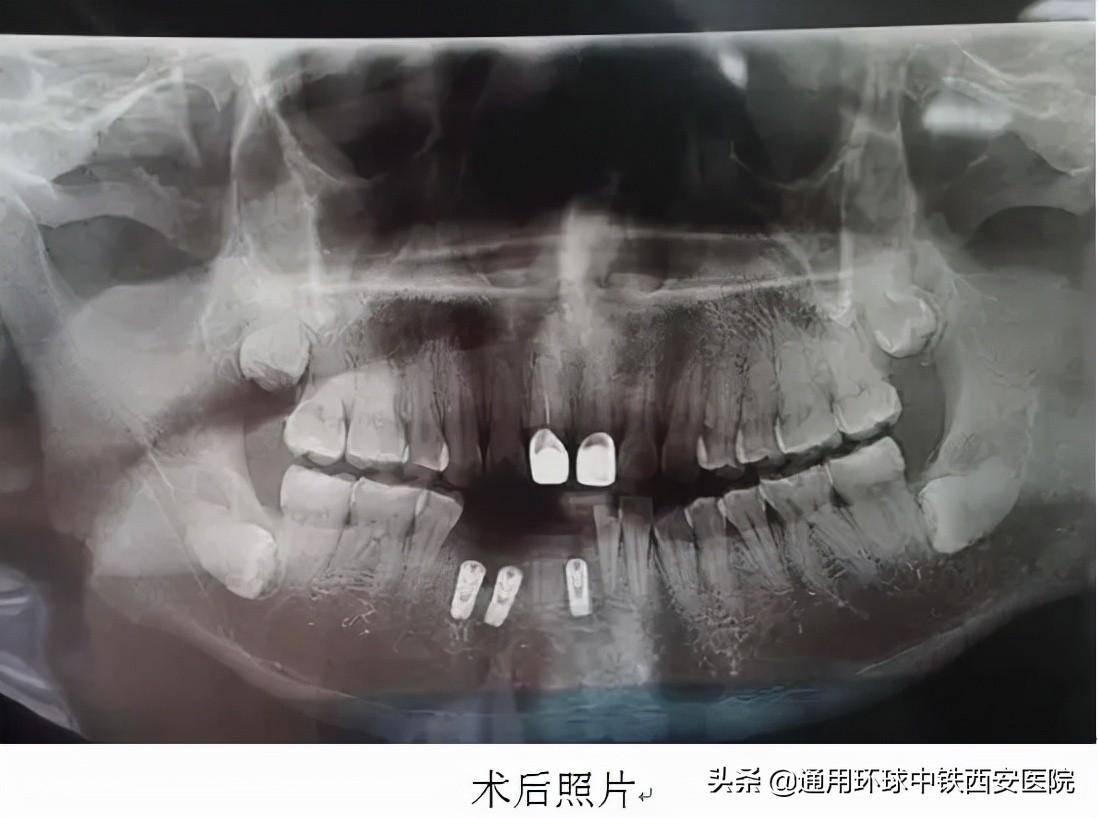

手術(shù)于9月22日進行,術(shù)前常規(guī)消毒鋪巾麻醉,微創(chuàng)拔除41、42、44牙殘根,在與術(shù)前規(guī)劃一致的位置分別植入直徑3.75mm,高度11.5mm、直徑4.2mm,高度11.5mm、直徑4.6mm,高度10mm的種植體,在唇側(cè)植入骨粉共0.25g。修整外形后。表面覆蓋可吸收生物膜,間斷嚴密縫合傷口。手術(shù)歷時約40分鐘,術(shù)后宋先生無不適。